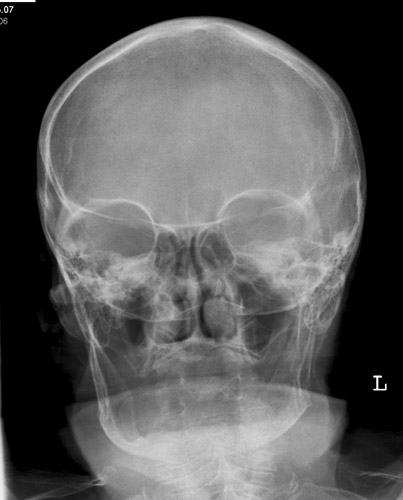

Schädel/Gesicht

Schädel a.p.

Fehler

Schräge Projektion, d.h. ungleicher Seitenabstand der Schädelkapsel vom Keilbeinflügel.

Abhilfe

Symmetrische Lagerung des Kopfes.